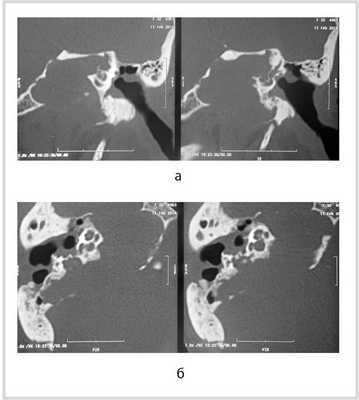

Рис. 1. КТ височных костей пациентки М. а — коронарная проекция: деструктивная полость в пирамиде височной кости, заполненная субстратом неоднородной плотности, капсула лабиринта значительно разрушена на уровне базального и апикального завитков улитки, латерального и верхнего полукружных каналов; б — аксиальная проекция: деструктивная полость с разрушением задней грани пирамиды, передневерхней и нижней поверхности.

По результатам МРТ головного мозга правая пирамида височной кости деформирована, увеличена в объеме, выполнена субстратом размером до 5,5—2,8—3 см, распространяющимся на область внутреннего слухового прохода, заднего полукружного канала, медиальные отделы барабанной полости, сосцевидный отросток. Описанный субстрат изо-гипоинтенсивен в режиме Т1, гиперинтенсивен — в Т2 и non-EPI DWI (рис. 2). Заключение: признаки рецидива холестеатомы с деструктивными изменениями структур внутреннего и среднего уха на фоне хронических воспалительных изменений.